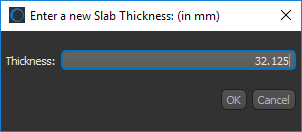

- Right-click inside the view in Slab mode and then choose Set Slab Thickness in the pop-up menu. You can then enter the required slab thickness in the Enter a New Slab Thickness dialog, as shown below.

- Right-click inside the view in Slab mode and then choose Set Slab Thickness in the pop-up menu. You can then enter the required slab thickness in the Enter a New Slab Thickness dialog, as shown below.